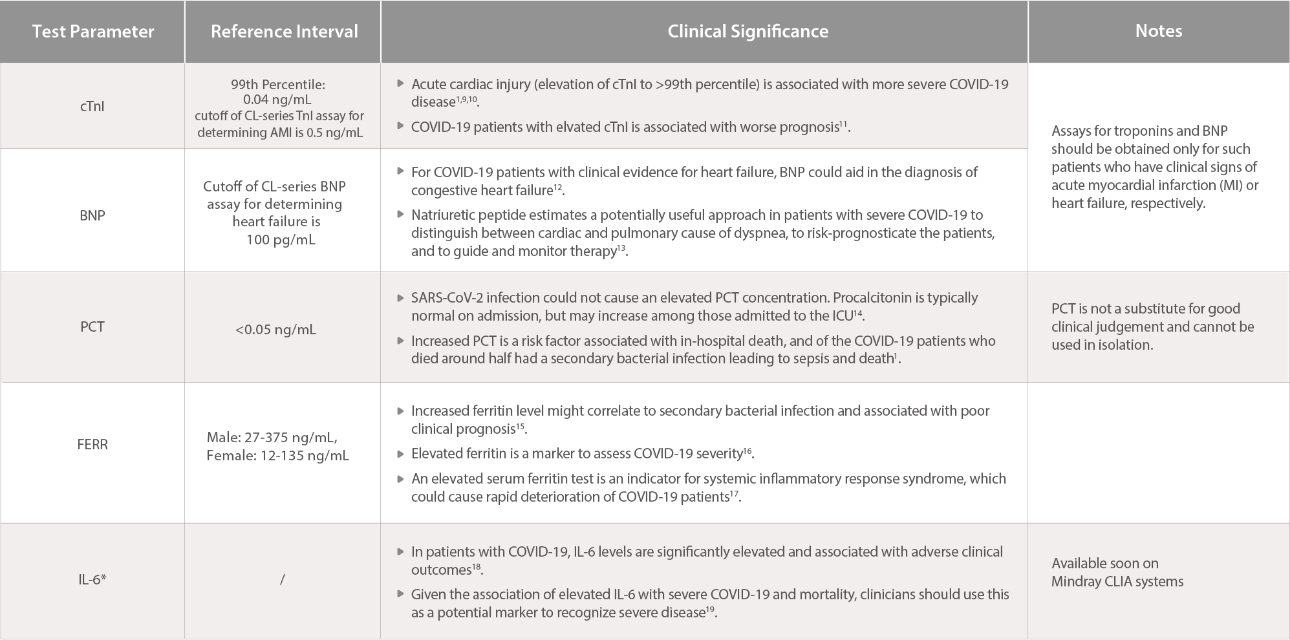

CLIA Test Indices

[10]. Lippi G., Lavie C.J., Sanchis-Gomar F. Cardiac troponin I in patients with coronavirus disease 2019 (COVID-19): Evidence from a meta-analysis. Prog Cardiovasc Dis, 2020.

[11]. Ruan Q., Yang K., Wang W., Jiang L., Song J. Clinical predictors of mortality due to COVID-19 based on an analysis of data of 150 patients, Intensive Care Med, 2020.

[12]. James L. Januzzi Jr. American College of Cardiology: Troponin and BNP use in COVID-19.

[13]. Kunal Mahajan, Prakash Chand Negi. The role of natriuretic peptide estimation in severe COVID-19.Monaldi Archives for Chest Disease, 2020.

[14]. Interim Clinical Guidance for Management of Patients with Confirmed Coronavirus Disease (COVID-19). US CDC.

[15]. Bo Zhou, et al. Utility of Ferritin, Procalcitonin, and C-reactive Protein in Severe Patients with 2019 Novel Coronavirus Disease.

[16]. Clinical guide for the management of critical care for adults with COVID-19 during the coronavirus pandemic. UK NHS.

[17]. Colafrancesco S, et al. COVID-19 gone bad: A new character in the spectrum of the hyperferritinemic syndrome?. Autoimmun Rev. 2020.

[18]. Coomes E, et al. Interleukin-6 in COVID-19: A Systematic Review and Meta-Analysis. doi: https://doi.org/10.1101/2020.03.30.20048058

[19]. Aziz M, Fatima R, Assaly R. Elevated Interleukin-6 and Severe COVID-19: A Meta-Analysis. J Med Virol. 2020.?